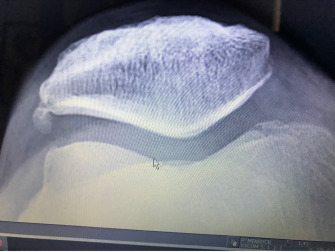

Physical exam involves provocative and alleviatory maneuvers as well as differential exclusion of other possible pain sources. Simple radiographs provide information regarding the presence of pre-mature arthritic change resultant of prior trauma. Positional asymmetries of the patella as it relates to the trochlear groove of the femur, and anatomic variants such as a shallow groove or non-prominent patellar ridge, calcified fragments, cysts, or spurs can all be ascertained via simple X-ray.

Below: “Sunrise view” of the PFJ with mild medial femoral condyle arthritis and a large   projection “spur” off the lateral facet patella.